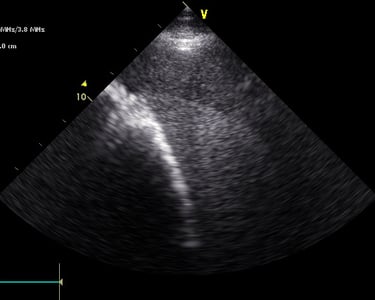

Heeft uw paard een hartruis? Dan is het aanbevolen om een echocardiografie (hartonderzoek) en een inspanningstest met elektrocardiogram (EKG) te laten uitvoeren. Zo kunnen we beoordelen of het veilig is om uw paard te berijden. Een hartruis is namelijk niet altijd een probleem. Met een echocardiografie onderzoeken we of het hart een normale structuur en werking heeft en bepalen we de ernst van eventuele klepafwijkingen.

Voor een uitgebreid hartonderzoek hoeft u niet langer naar een kliniek. Zowel de echocardiografie als de inspanningstest met elektrocardiogram kunnen eenvoudig bij u ter plaatse worden uitgevoerd.

Hartonderzoek - Echocardiografie - Electrocardiografie (EKG)